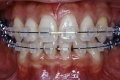

初診時

|